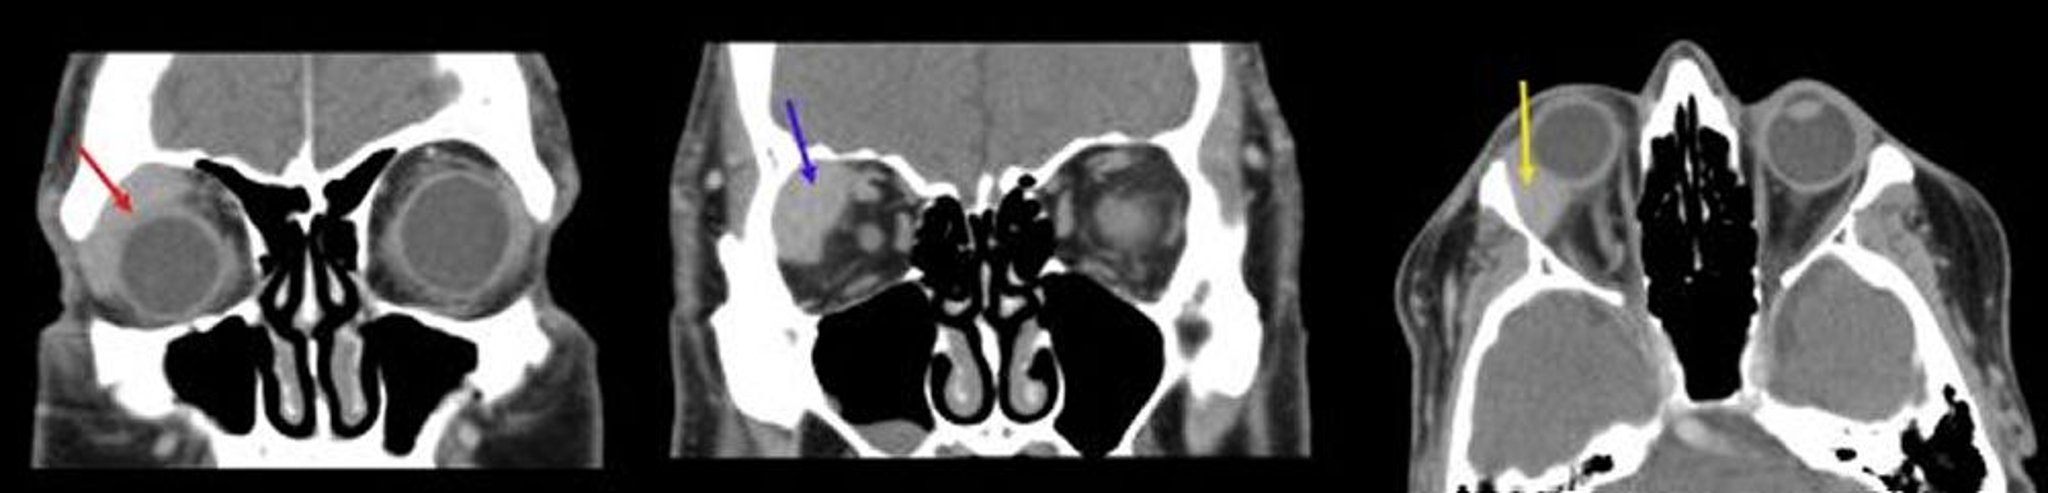

Orbitales Lymphom

Auf dieser Abbildung zeigt die erste koronale CT-Aufnahme (links) eine homogene Masse, die sich dem Augapfel anpasst (roter Pfeil). Die zweite koronale CT-Aufnahme (Mitte) zeigt eine gut abgegrenzte Raumforderung in der rechten Fossa der Tränendrüse (blauer Pfeil). Die axiale CT-Aufnahme (rechts) zeigt eine homogene Masse in der Fossa lacrimalis, die dem rechten Augapfel entspricht (gelber Pfeil).

Images courtesy of James Garrity, MD.